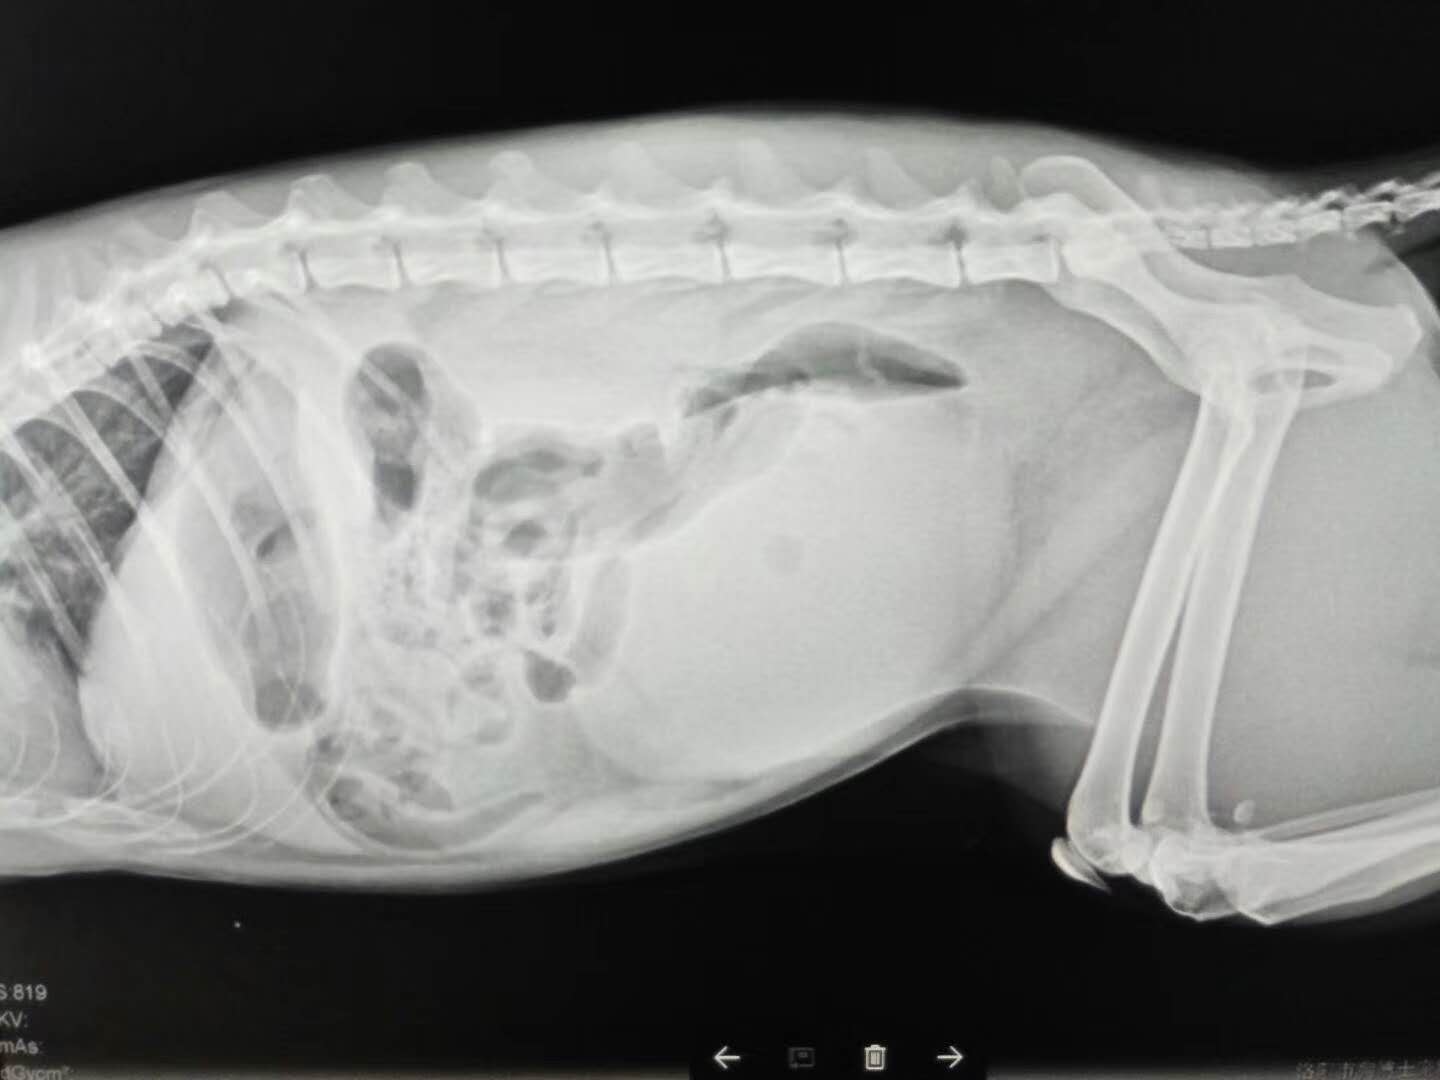

肉絲(美短),已經(jīng)好幾天不見尿了。主人有一定的飼養(yǎng)經(jīng)驗(yàn),懷疑肉絲得了貓咪下泌尿道綜合征,遂帶至我院,進(jìn)行檢查。緊急導(dǎo)尿管導(dǎo)尿,導(dǎo)出大量血尿?,F(xiàn)在已經(jīng)開始吃東西喝水了。